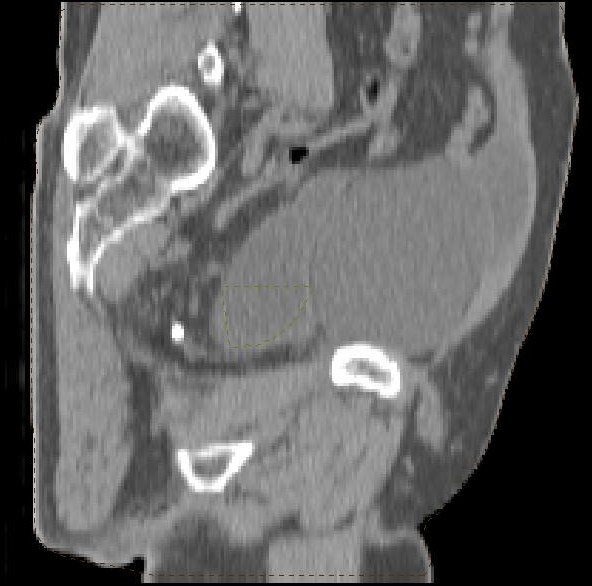

postoperative Lymphozele

Große Lymphozelen nach laparoskopischer pelviner Lymphonodektomie.